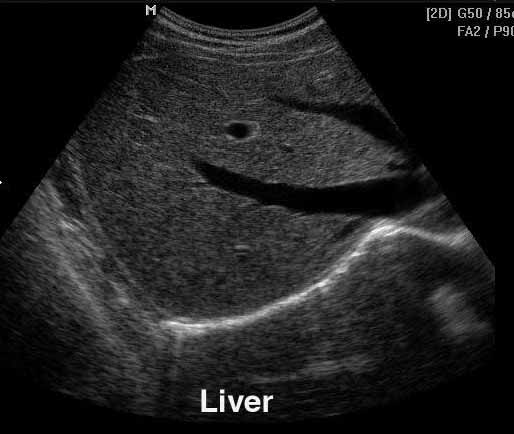

Refer to caption

(b) Liver

Figure 1: Example ultrasound images from the cardiac (a), gastric (b), fetal (c) and Blood flow (d) domain.

Different anatomic regions have different characteristics in ultrasound images, as can be seen in Figure 1. For instance, in a liver scan one might look for tumors using a high-resolution abdominal 2D probe. For heart infarctions, the doctor might need to examine the strain in the heart muscle to detect defect muscle tissue. The wide spread in tissue and pathology difference lead to anatomically specific visualization techniques.